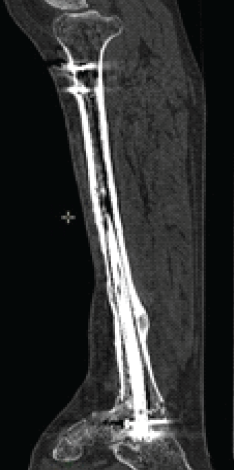

We opted for an anterograde tibiotalar intramedullary nailing with a conventional tibial nail, ensuring tibiotalar arthrodesis with stable static fixation at proximal tibial and talar level (Fig. 5).

Figure 5: Post-operative X-ray, distal tibia allograft, and anterograde tibia–talus intramedullary nailing